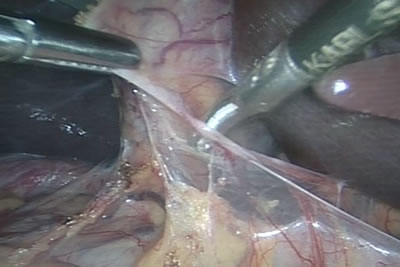

Рассекается париетальная брюшина для доступа к правой почке.

При рассечении брюшины активно используется аппарат LigaSure.

Идет рассечение париетальной брюшины по правому боковому

каналу.